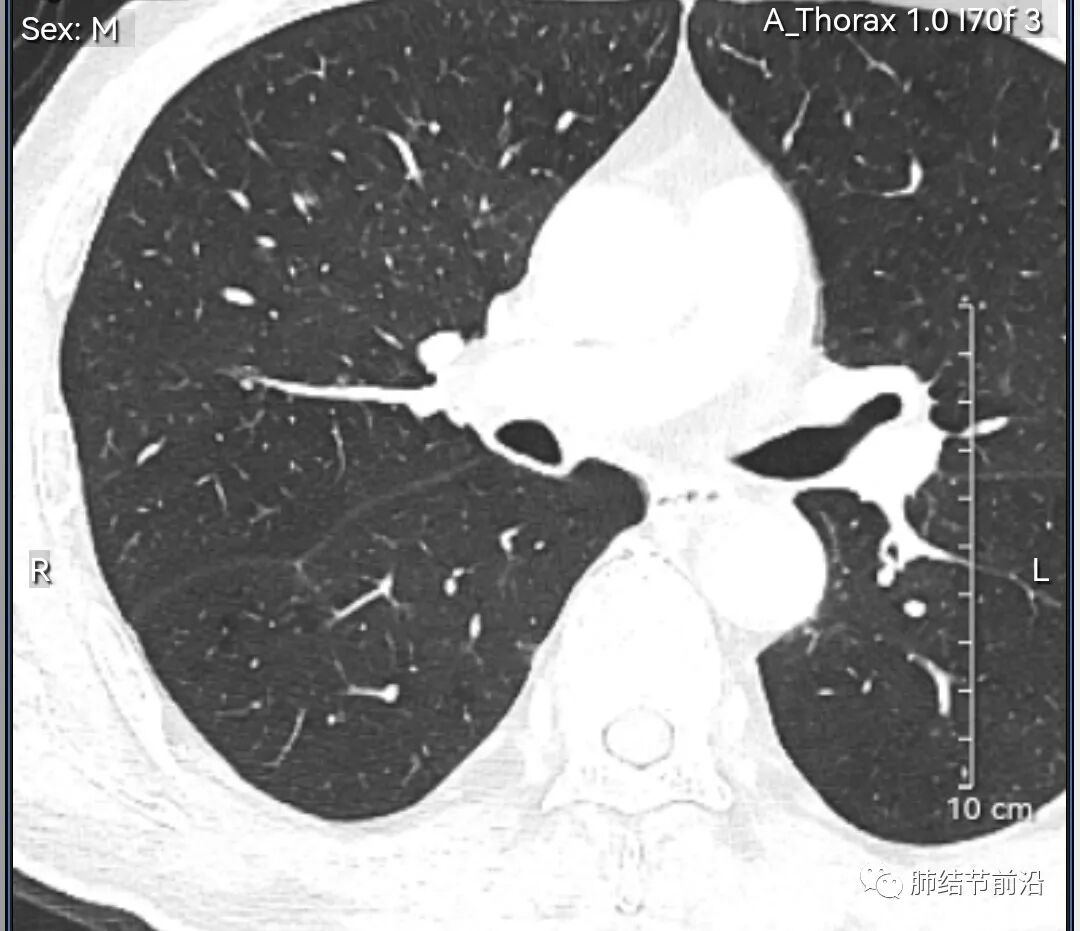

男性,67岁,重度吸烟史。CT发现右下肺囊腔。来看一下这个CT的特点:

该囊腔形态非常有特点,和常见的圆形肺大泡有很大的区别。

1.囊腔中央实性成分,周围有磨玻璃影。

2.囊腔中央有血管。

3.囊腔外周有分叶形态。

4.囊腔有胸膜牵拉。

出现这几种形态,CT可以确认恶性的腺癌。这个囊腔形成的机制,为肿瘤实性成分堵塞细支气管形成活瓣,肺泡内压力增高破裂行成,因此肺内血管成分保留。由于肺泡压力增高,而呈分叶状。另外,也有肿瘤的胸膜牵拉这一特点。

囊腔周围磨玻璃+囊腔中央血管为特征性表现。如果持续存在,几乎可以100%确认为早期肺腺癌。

建议患者手术切除,术后病理为浸润性腺癌,腺泡型,部分为实体型。IA1期,术后不用治疗。